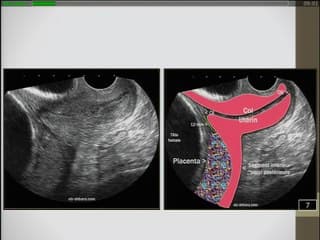

Revue des aspects échographiques des cicatrices utérines au 1er trimestre de la grossesse ainsi que leur classification. La communication de Catherine EGOROFF insiste bien sur l'importance de l'examen du col, de l'isthme utérin et de la localisation placentaire par voie endo-vaginale au 1er trimestre de la grossesse en cas d'antécédent de césarienne pour le dépistage des cicatrices à risque et des placenta accreta